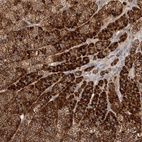

Immunohistochemical staining of human adrenal gland shows strong positivity in cortical cells.